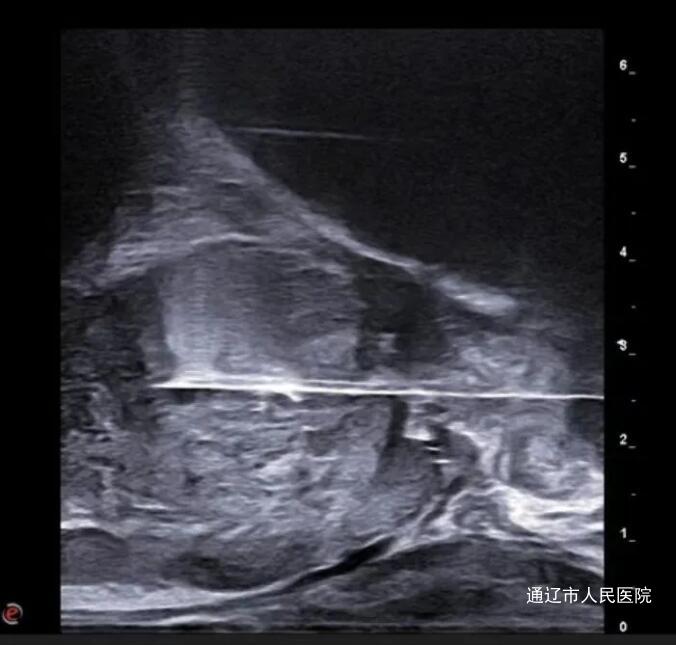

自上月起,我院东区超声医学科成功开展7例经会阴前列腺穿刺活检术,填补了我市该领域技术空白,标志着我院在前列腺癌早期诊断与治疗领域迈出了坚实一步。

前列腺癌,作为男性泌尿生殖系统中最为常见的恶性肿瘤之一,其全球发病率高居男性恶性肿瘤第二位,且近年来呈明显上升趋势。面对这一严峻挑战,早期诊断与及时治疗对于改善患者预后、提高患者生活质量具有不可估量的健康价值。在此背景下,我院东区超声医学科紧跟国际前沿,引入了经会阴前列腺穿刺活检术这一先进技术。相较于传统的经直肠穿刺途径,经会阴穿刺术无需繁琐的肠道准备,其优势具体体现在显著降低了尿道损伤、术后感染及出血风险上,为患者带来更加安全、舒适的检查体验。尤为重要的是,该技术能够更加有效地触及并取样前列腺外周带组织,而该区域恰恰是前列腺癌的高发部位,从而大大提高了诊断的准确率与可靠性。此次技术的升级,不仅是对“经直肠前列腺穿刺活检术”的一次重要补充与超越,更是积极响应了《前列腺穿刺中国专家共识(2022年版)》中的最新理念,即经会阴途径应作为前列腺穿刺活检的首选方案之一。未来,我院东区超声医学科将继续秉承“科技让医疗更简单”的医疗信仰,不断探索与引进国际先进的医疗技术,致力于前列腺癌及其他泌尿生殖系统疾病的早诊早治,为守护男性健康贡献更多力量。